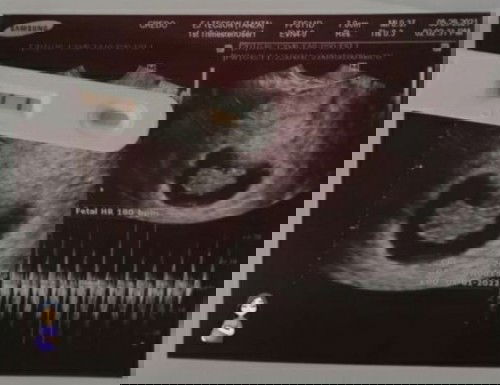

My first baby #firstbaby after trying and trying I’m finally pregnant ❤️🙌🏻